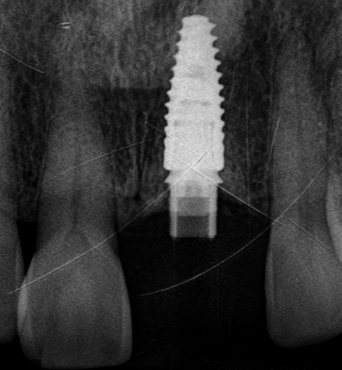

정밀 진단 및 모의 시술

구강 스캔 · CT · X-RAY로

뼈와 신경 위치를 확인

리봄치과의 임상증례 공개는 자신감입니다.

BEFORE & AFTER

01임플란트2023.06.02 - 2025.03.26

BeforeAfter